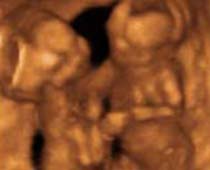

- 3D Photos échographie de grossesse multiple